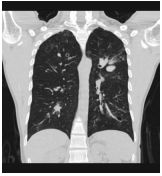

4. 39 y/o female, productive cough for 2 months